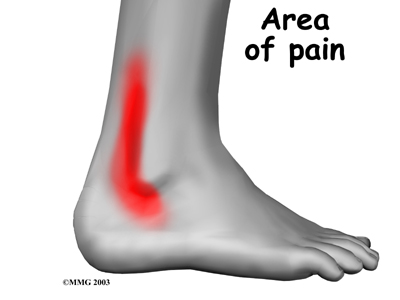

Patients with peroneal tendon problems usually describe pain in the of the ankle or just behind the lateral malleolus. This pain commonly worsens with activity and eases with rest. Patients may have swelling behind or under the lateral malleolus. They may notice more pain when pressure is applied along the tendons.